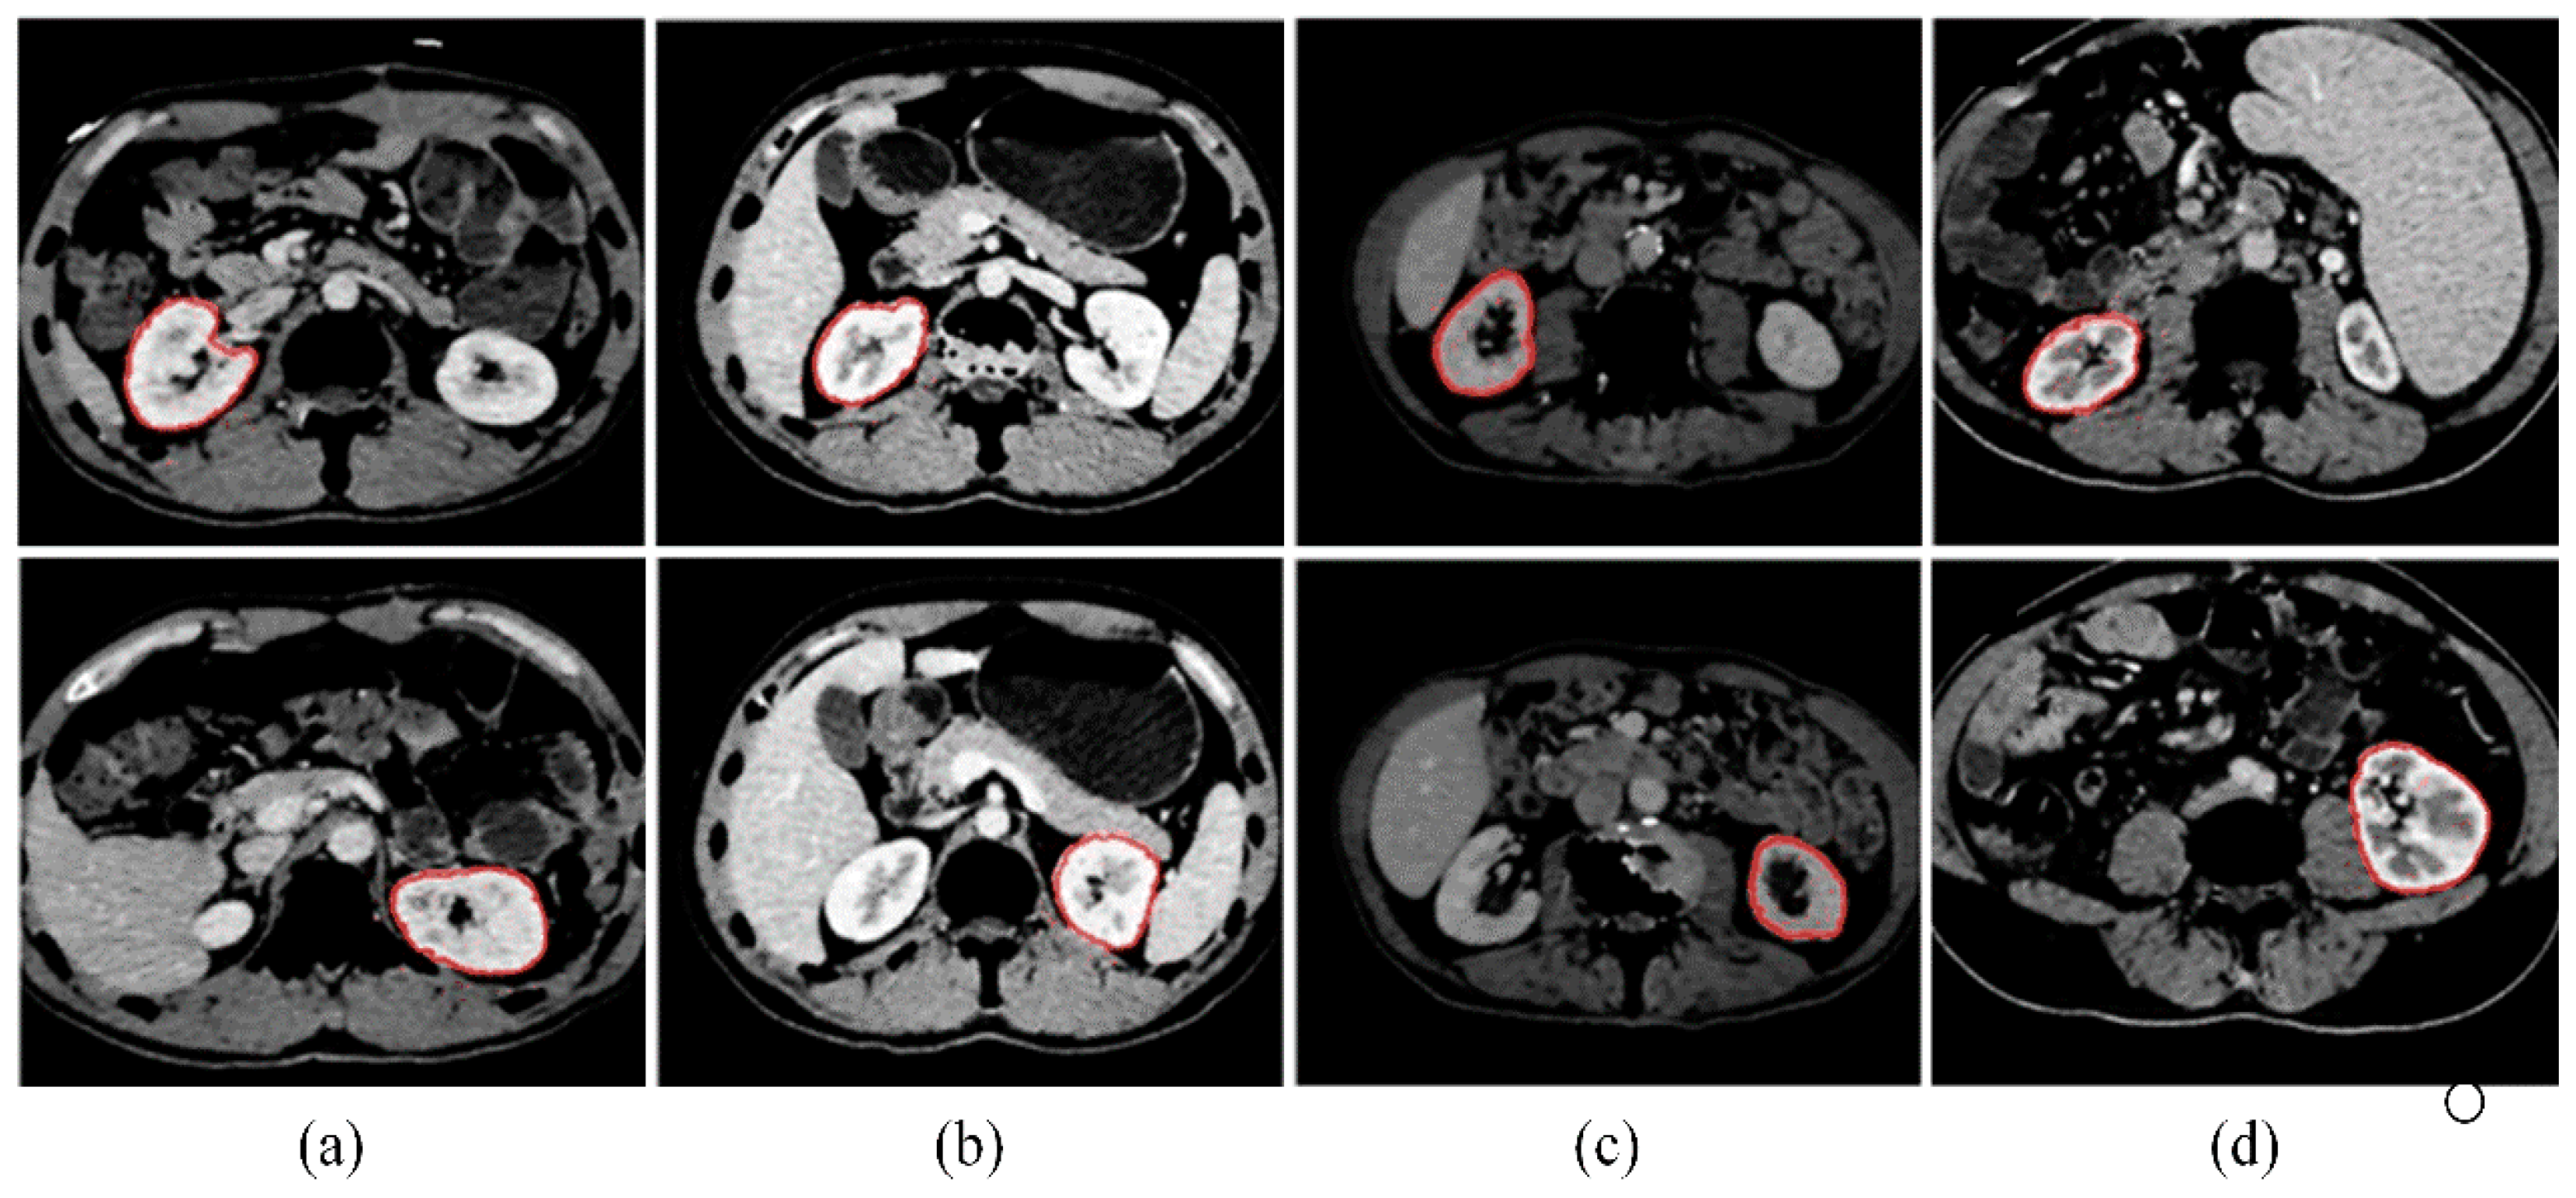

Through the above strategy, we select a kidney with a large area and a clear boundary as the initial contour and assume its slice as the initial segmentation slice. Figure 7 shows the search results of the initial kidney contours from four sequences. The first row displays the left kidney contour, and the second row displays the right.

Figure 7. (ad) Automatic searching results of the initial kidney contours from four sequences. The first row displays the left kidney contour, and the second row displays the right. The red outline represents the initial contour results.